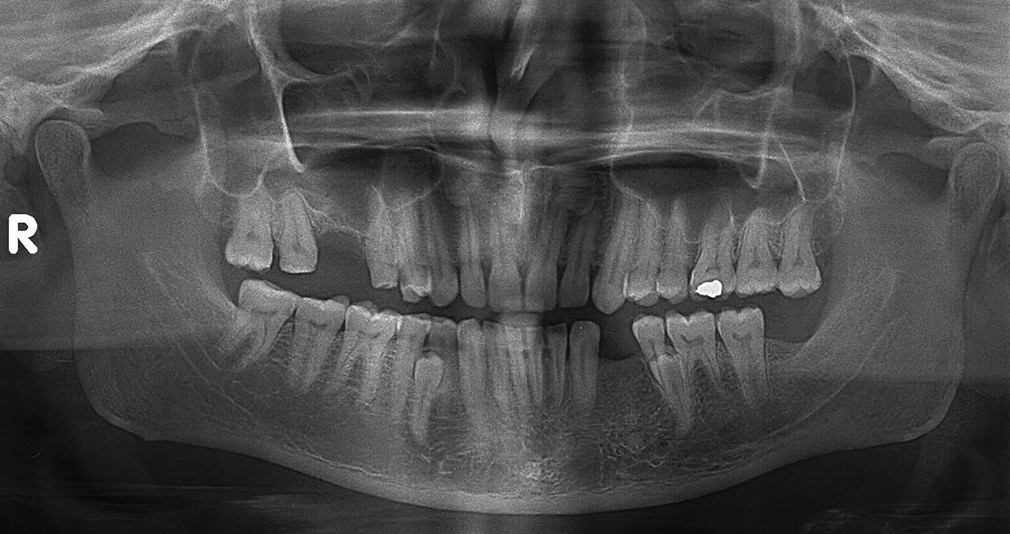

Mandibular bilateral unerupted non-obstructing supernumerary premolars as a rare paradental anomaly |

p. 204 |

Vineet Gupta, Puneet Kumar, Prince Kumar, Nishant Lakhani DOI:10.4103/2278-9626.105389 Non-syndromal multiple supernumerary teeth are most commonly seen in mandibular premolars region, followed by the molar and the anterior regions respectively. Dental literature rarely reports symmetrical supernumerary teeth in all four quadrants. However, supernumerary premolars may not become radiographically visible until the patient's normal premolars have erupted. This article presents a case of a 45-year-old male with bilateral unerupted fully formed, buccally angulated, supernumerary premolars in the mandibular region without any obstruction to the eruption of mandibular first and second premolars. There was no syndrome associated. The delayed development of the supernumerary teeth in the premolar region supports the hypothesis that these teeth were part of a post-permanent dentition. |